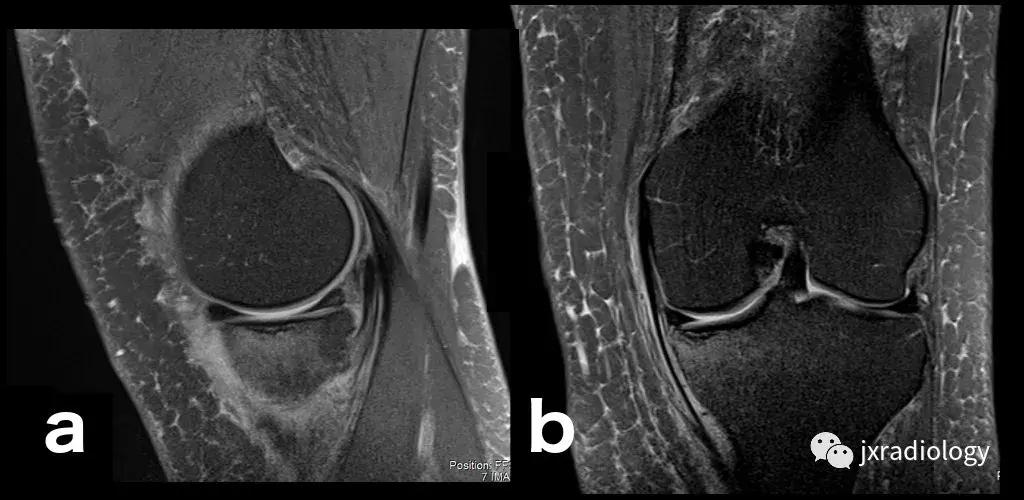

图2:骨性关节炎(OA):男,58岁,股骨内侧髁负重区有软骨缺损,伴有边缘小骨赘和继发性软骨下骨髓水肿。骨性关节炎通常不与创伤性病因分类,而是作为退行性病变分类(a:冠状T1-WI; b:冠状PDWI-FS; c:矢状PDWI-FS)。